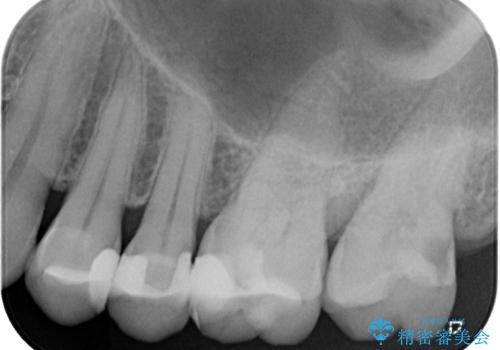

- 奥歯がかけてしまい、しみるようになったとのことで来院された患者様です。

上顎奥の粘膜に近い部分で、つめものの下には大きく虫歯が広がっていました。

虫歯をしっかりと取り除き、ゴールドインレーにて修復することとしました。